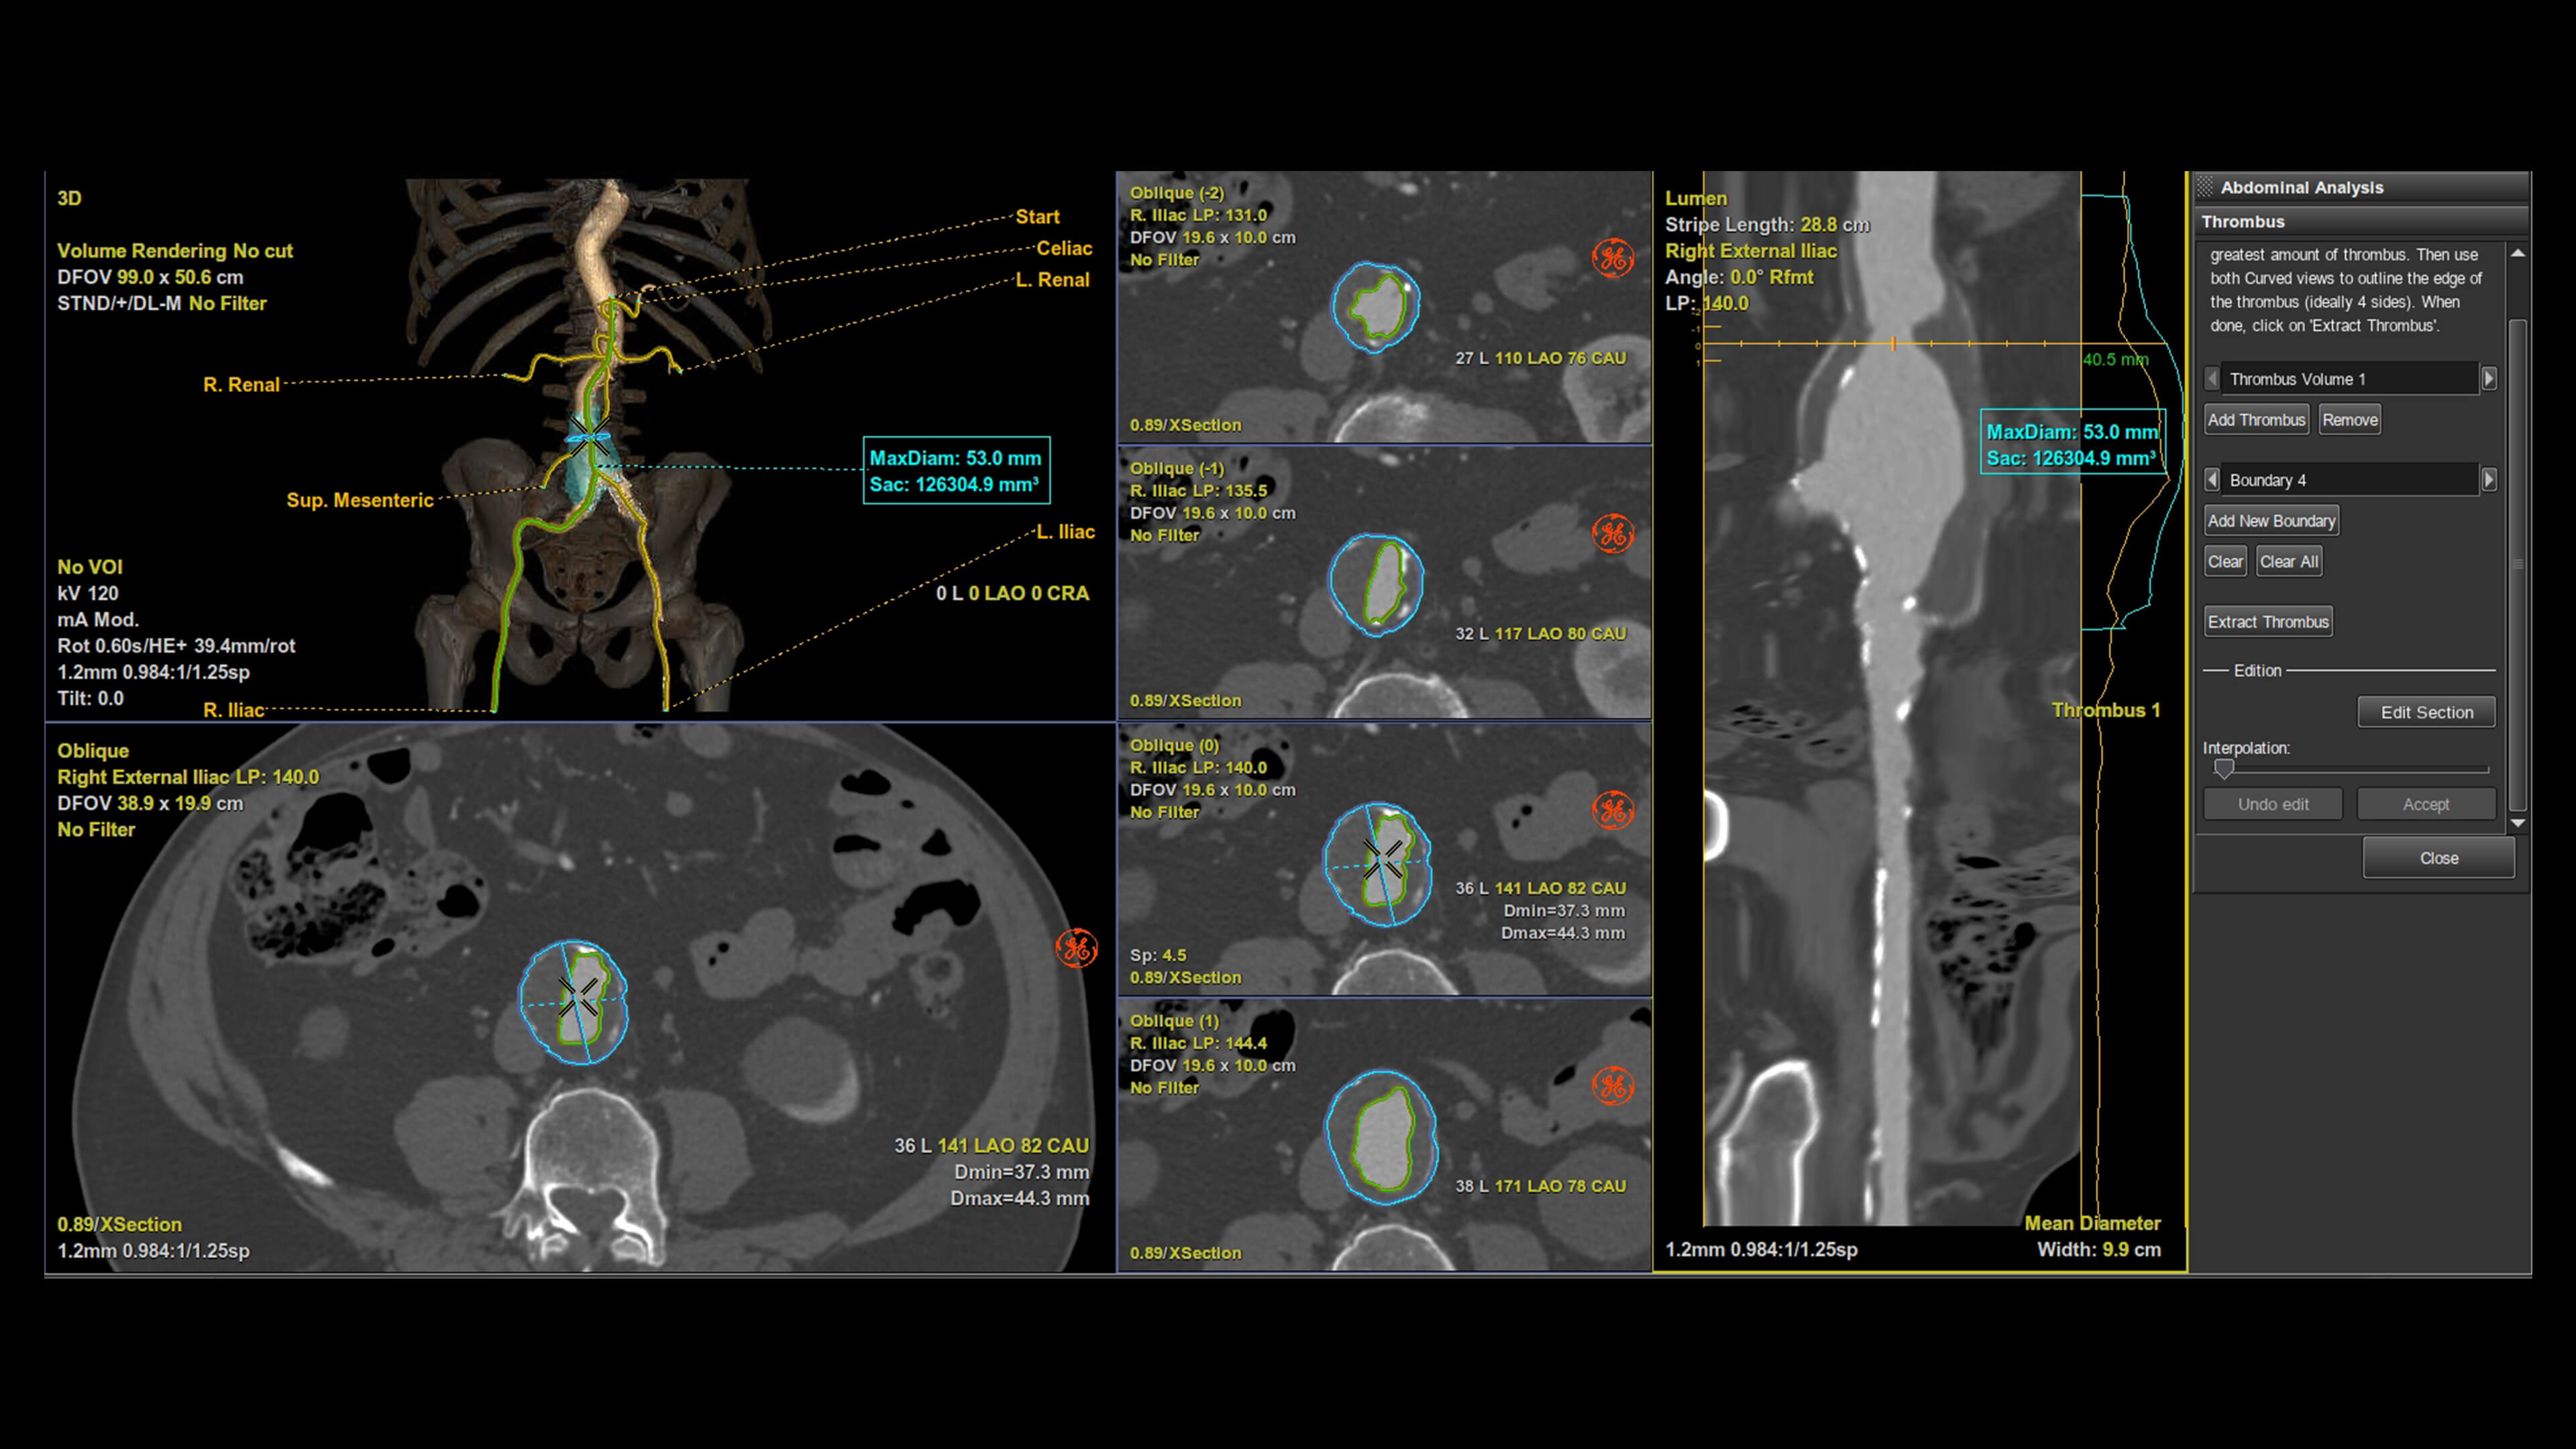

Autobone & VesselIQ Xpress

Fast and efficient vessel analysis from CT Angiography exams.

Automated detection of aorta and illiacs with auto-labeling of vessels

Comprehensive stenosis measurement and plaque analysis of any vasculature

• Thrombus detection with measurements and comparison over time.